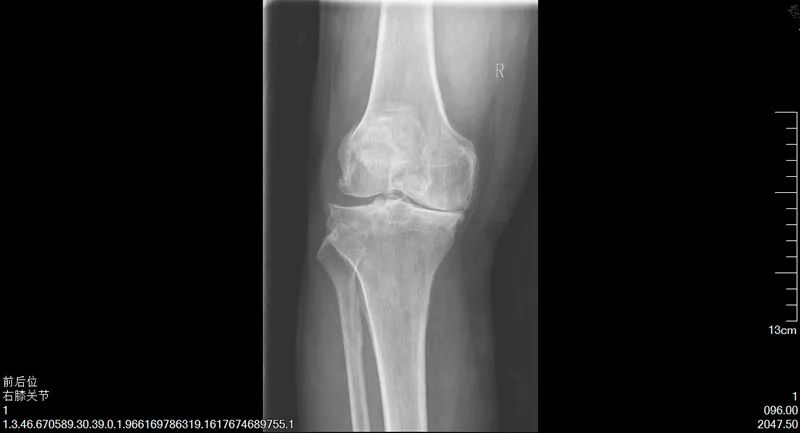

陳阿姨的故事,說來還要將時間追溯至十年前,陳阿姨常年操持家中的生意,雙膝落下了問題,時常疼痛難忍,后來甚至發(fā)展至不能正常行走。這時,鄰居常大哥告訴她,可以試試到市第一人民醫(yī)院看看。隨即,陳阿姨來到了我院骨科二病區(qū)找到了楊勇主任,做了雙側(cè)人工全膝關(guān)節(jié)置換術(shù),術(shù)后恢復(fù)得非常好,雙腿和正常人無異,既不疼了,也能站直了。時至今日,陳阿姨說她的腿依然健康如初,每天可以去跳廣場舞,生活質(zhì)量得到了顯著提高。

手術(shù)前